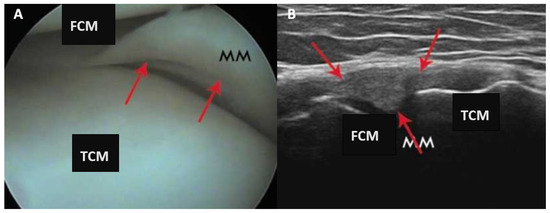

A sample of arthroscopic vs ultrasound view estimation is seen in the Figure 3. (A) arthroscopy view: morphology of injury present (1). (B) ultrasound examination: change in shape morphology - 2; evaluation of capsular attachment - 1; evaluation of bone meniscus attachment - 0; articular space stenosis - 0; morphology of meniscus injury - 1.

Figure 3. Arthroscopy and ultrasound examination results analysis of longitudinal, stable medial meniscus tear. (A) Arthroscopy view; (B) presentation of ultrasound examination.

In the clinical part of the study, arthroscopic examination revealed 13 longitudinal injuries (corresponding to 36% of all injuries in the group), 14 multidirectional injuries (corresponding to 28% of all injuries), 3 radial injuries (corresponding to 6% of all injuries), and 20 oblique injuries (corresponding to 40% of all injuries). Figure 4 presents arthroscopy and ultrasound views of a longitudinal, stable tear of the medial meniscus. (A) arthroscopy view: morphology of injury present (1). (B) ultrasound examination: change in shape morphology - 1; evaluation of capsular attachment - 1; evaluation of bone meniscus attachment - 0; articular space stenosis - 0; morphology of meniscus injury - 2.

Figure 4. Clinical part of the study of a longitudinal, stable tear of the medial meniscus. (A) Presentation of arthroscopy view; (B) presentation of ultrasound examination. MM—medial meniscus; FCM—femur medial condyle; TCM—tibial medial condyle. Red arrows indicate damage to the meniscus in arthroscopic and ultrasound view.